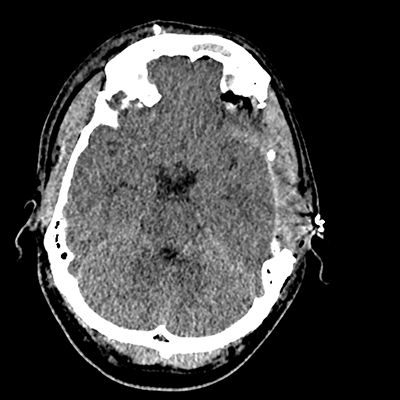

On day 5 of admission, he begins having intracranial hypertension again, spiking up to 40mmHg. You bolus with propofol and fentanyl, to no avail. You then push 30mL of 23.4% NaCl, which provides some brief improvement, allowing you to quickly get a non-contrast head CT. Unfortunately, he's now back up to 36mmHg. You review his labs, and note the following: Na 150, K 3.8, Cl 119, HCO3 18, BUN 21, Cr 0.85, glucose 136, sOsm 320.

NCHCT

NCHCT 1/20 1/20